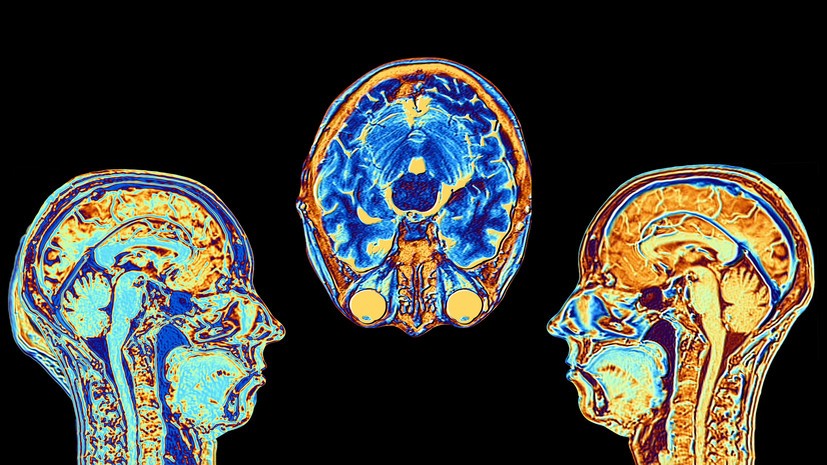

- Gettyimages.ru

- © ALFRED PASIEKA/SCIENCE PHOTO LIBRARY